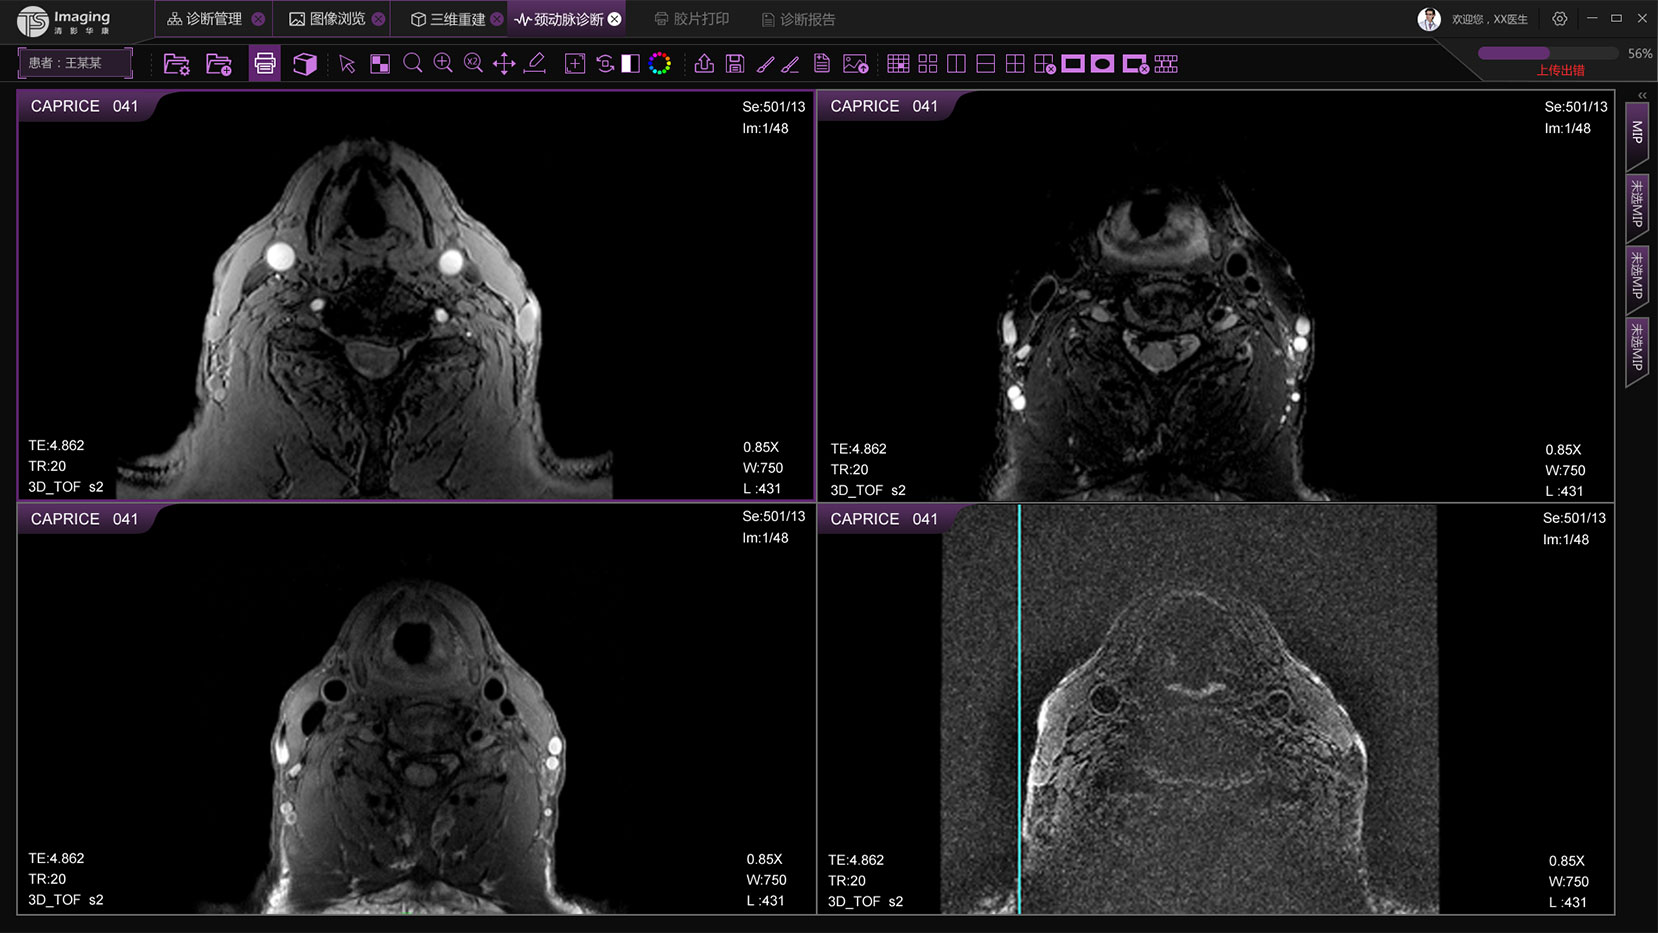

頸動脈診斷頁面

頸動脈診斷頁面整體布局和三維重建比較相似,最大的區別是右側的操作區域,血管分析都為按鍵操作,通過間隔的大小分成三部分。單層切片除了按鍵還有下拉菜單的操作。